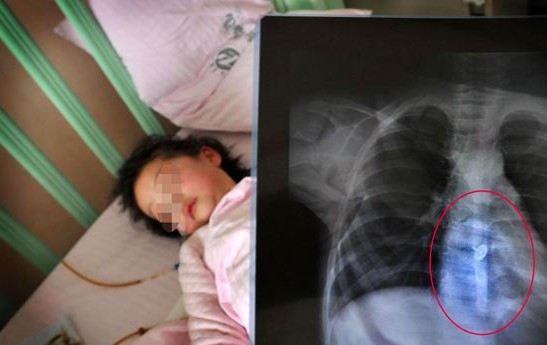

日前,家住东莞凤岗、9个月大的男婴误喝农药赛丹,经医院抢救侥幸捡回一条性命。

6日上午,9个月大的阳阳哭闹不止,妈妈李女士刚好有事走开了。两岁多的姐姐见他哭得厉害,以为弟弟肚子饿了,就从屋子里找来一瓶“水”,学妈妈的样喂他,哄住阳阳不哭了。“我回来后见状马上夺过女孩手里的瓶子,一看包装瓶上写着‘赛丹’(一种杀虫农药),抱起阳阳就往医院跑。”李女士心有余悸地回忆。

入院时阳阳烦躁不安,神志模糊,口腔、唇周边及胸前均可见少量农药残留,味道刺鼻,后来多次出现四肢痉挛性不自主抽搐。到下午1时许,患儿抽搐症状得到基本控制,意识开始慢慢恢复,目前未见心、肝、肾、脑等明显并发症及其他脏器损害。据了解,误服化学药水、药物等发生中毒的,多见于0至4岁儿童。毒物有灭鼠药、有机农药及煤油、汽油、油漆等。医生指出,儿童服入有毒的东西多是大人管理不善所致,因此,家长一定要保管好家中的有毒物品。